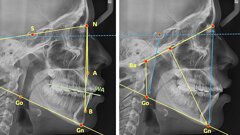

- Parodontalna anestezija u tretmanu ireverzibilnog pulpitisa molara mandibule 04 - 24

- Parodontalna anestezija u tretmanu ireverzibilnog pulpitisa molara mandibule 06 - 09